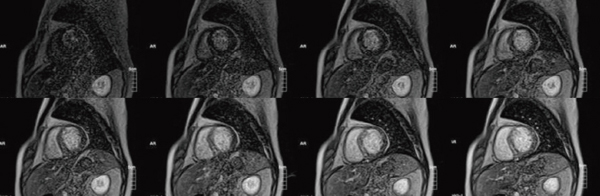

高い時間分解能を生かしたシネ撮像法による心機能解析や,造影剤投与後,十数分待って撮像することにより,心筋梗塞部位などを明瞭に描出できる遅延造影撮像法も良好な画像が得られる(図3)。さて,遅延造影撮像法においては,心筋の信号値がゼロ近くになるTI(Inversion Time)を,撮像時の条件設定で決定しなければならない。このとき,TIを変えながら複数の画像を撮像してTI値を決定する“TI-prep”機能を用いることで,設定すべきTI値を容易に求めることが可能となった(図4)。ここで重要なのは,インバージョンパルスによって反転された縦磁化が回復する際,実際の撮像では,撮像に用いるRFパルスによって,縦磁化の回復曲線が変形を起こすことである。これが原因となり,TI-prepで求めたTI値と実際の撮像でのTI値が異なる場合がある。そこで,遅延造影撮像のシーケンスそのものにTI-prep機能を適用することで,正しいTI値を容易に,かつ正確に求めることを実現している。

図3 陳旧性心筋梗塞(OMI)